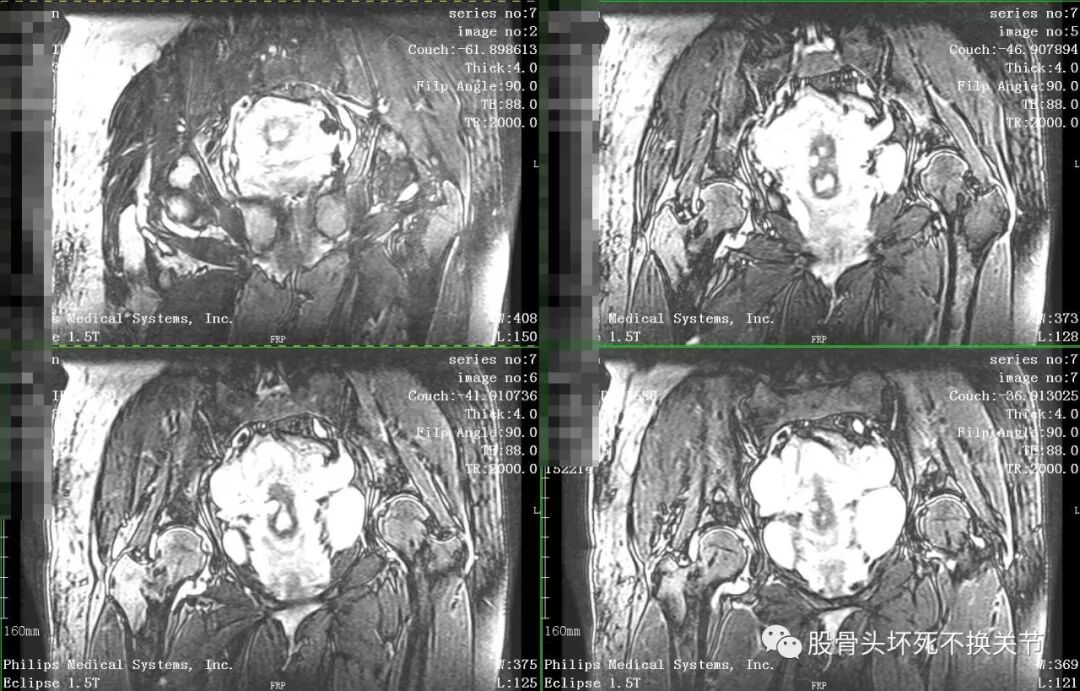

核磁共振是诊断疑难疾病的必备检查,更是诊断滑膜炎最直观、生动的手段。

点击放大观看双侧髋关节核磁共振片:

核磁共振检查显示右侧股骨头周围一圈亮度均匀的白色信号,就是平常所说的关节积液。